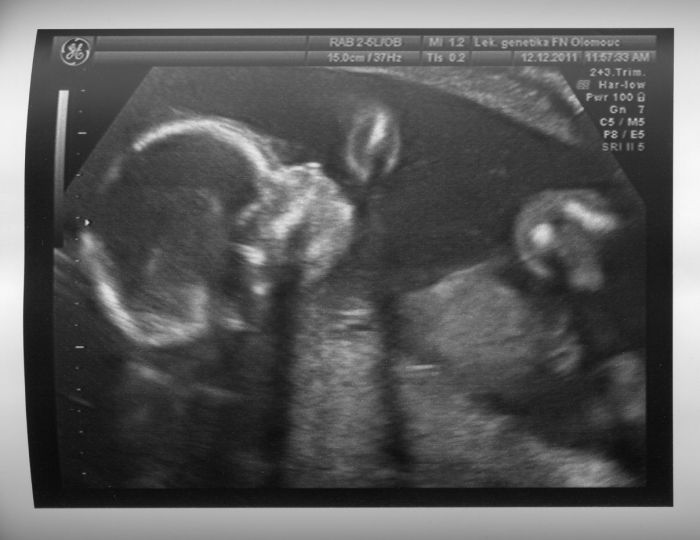

Ahoj holky, omlouvám se, že vám sem tak lezu. Byla jsem na dubnovkách, pač jsme měli termín 27.4., ale po včerejším velkém UV nám paní doktorka termín posunula na 1.5., tak vám píšu sem :-) Mě je 22, takže nejsem o moc starší jak Naja a Klára

Máte pravdu, je to nádhera ten zázrak vidět na UV, jak se tam hemží a u toho ho cítit. Já už mám pohyby skoro 2 týdna a zesiluje to, tak sem zvědavá, jak to bude vypadat ke konci těhu

Paní doktorka sice nebyla moc sdílná, ale viděla jsem páteř, ručky, nožky, hlavičku i pusinku (tu má úplně stejnou jako manžel

) A na poslední chvíli jsem se stihla zeptat i na pohlaví a budeme mít holčičku

Tak ať se vám daří a všechny kontroly vyjdou na jedničku

P.S. Přikládám fotečku té naší princezny